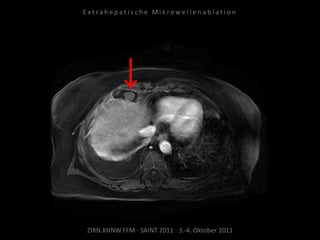

Kontrollbildgebung:

MRT 10.09.2010

Verlaufskontrolle:

CT 21.10.2010

MRT 21.01.2011

MRT 08.04.2011

Zunehmende Tumoraktivität der

Metastase kaudal der linken Niere

ohne signifikante Größenzunahme.